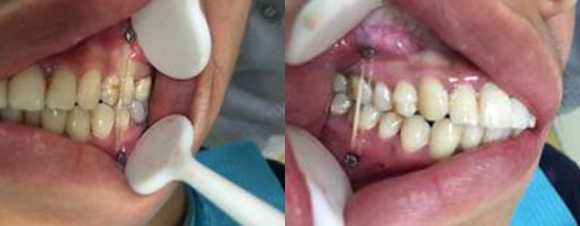

双侧后牙早接触前牙开牙合

双侧牵引钉颌间牵引

牵引后咬合关系恢复良好